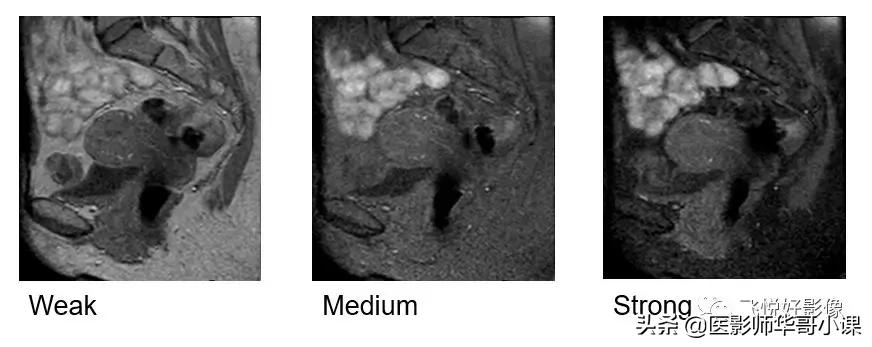

同时,也可以对脂肪抑制强度进行设置:

weak、medium、strong